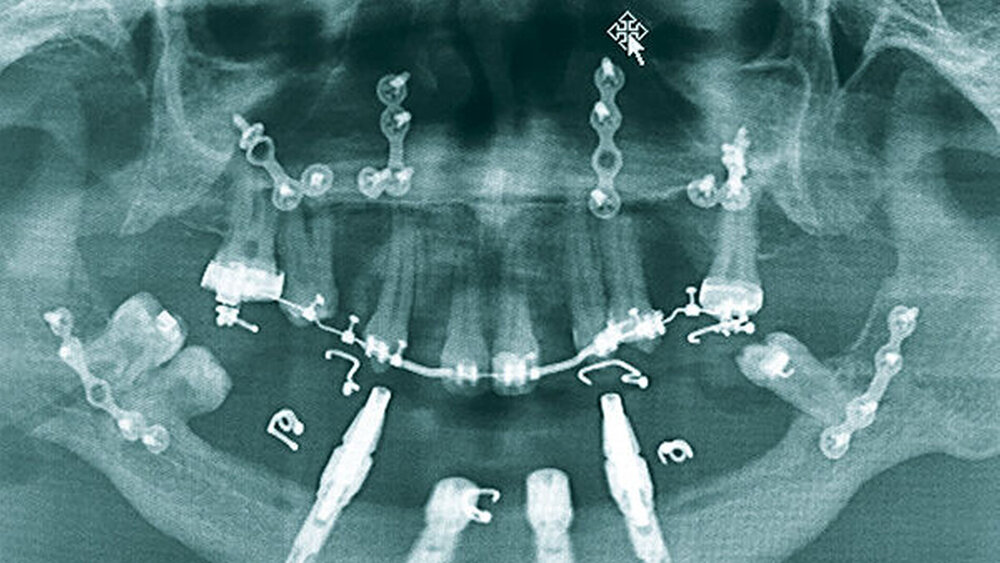

Zu Therapiebeginn im Alter von 20 Jahren zeigte sich eine skelettale Klasse III mit transversaler, vertikaler und sagittaler Unterentwicklung der Maxilla. Im Oberkiefer war die Zahnanzahl deutlich reduziert. Der Unterkiefer war nahezu zahnlos, hier waren außerdem der Alveolarfortsatz und die attached Gingiva stark atrophiert (Abbildungen 1 bis 3).

Vor der prothetischen Rehabilitation war dementsprechend eine kieferorthopädische und kieferchirurgische Vorbehandlung mit dem Ziel der dreidimensionalen skelettalen und dentalen Harmonisierung zwingend indiziert. Zunächst wurden die kariös zerstörten Zähne 14, 22 und 36 sowie die verlagerten Zähne 24 und 38 entfernt. Im Oberkiefer wurde eine kieferorthopädische Therapie eingeleitet, um den Zahnbogen auszuformen. Hierbei wurde eine Lückenöffnung in den Regiones 012 und 022 mit Protrusion der Zähne 11 und 21 vorgenommen. Im Anschluss konnte schließlich im Unterkiefer eine interforaminäre Insertion von vier Implantaten erfolgen (Abbildung 4).